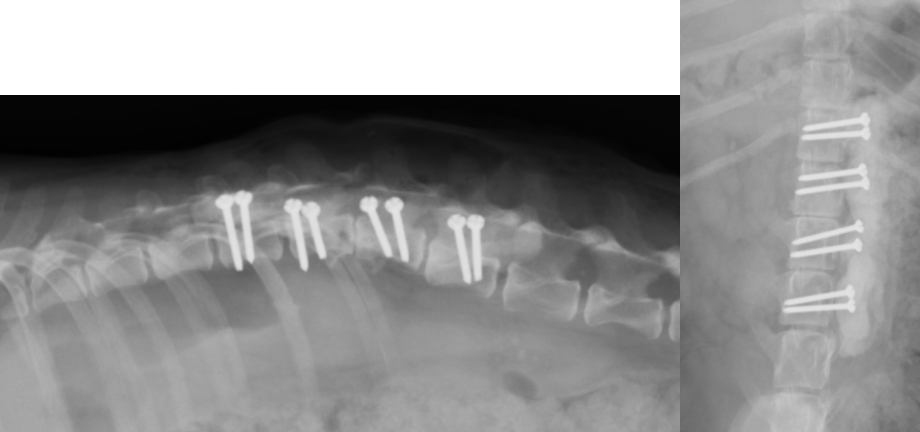

椎体骨折・椎体不安定に対する椎体固定術

交通事故などで背骨が折れてしまったり、椎間板の問題でズレが生じ不安定性がある場合、背骨の中を通る脊髄に障害をきたし、歩行異常や麻痺などの症状が出ます。また、大きな血管を損傷し、死に至る場合もあります。椎体骨折や椎体不安定の場合、椎体を何らかの方法で固定し、元の位置に安定化させる必要があります。小型犬〜中型犬で安全性が高く強固な固定は、折れている(ずれている)背骨とその前後の椎体にスクリューを打ち込み、打ち込んだスクリューを骨セメント(PMMA)という物質で固める方法です。他にもプレートやピンを使用する方法もあります。 手術自体は難易度が高いのですが、Cアームという透視装置を導入したことで以前ほどの危険性はなくなりました。

交通事故で椎体骨折した症例です。左右からスクリューを打ち込み、そのスクリューを骨セメントで固定することで、背骨のグラつきをなくしています。現在では走って診察室に入ってくるくらい元気に飛び回っています。